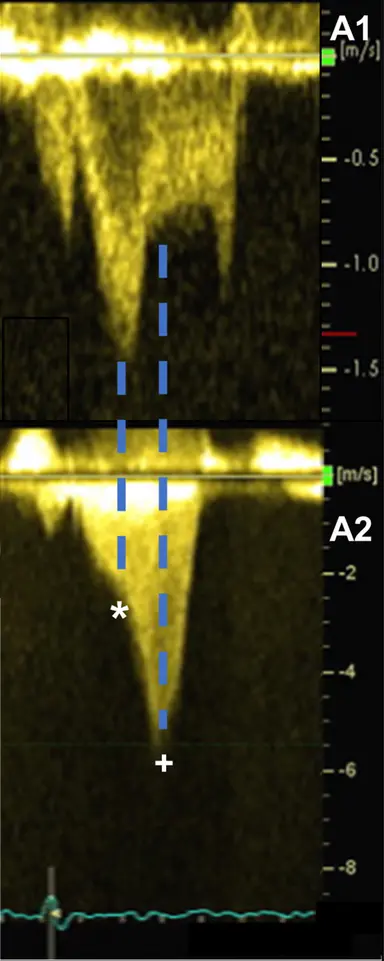

The degree of resting LVOT obstruction has been shown to be directly proportional to the degree of MR associated with SAM.1

LVOT obstruction is assessed using Continuous Wave Doppler-derived peak instantaneous gradient

LVOT gradient ≥ 50 mm Hg (at rest or with provocation) identifies severe obstruction and often serves as a threshold for pursuing septal reduction therapy or initiation of myosin inhibitor therapy.

Classically described as having a “dagger”-shaped appearance, but honestly resembles more of a nonworking upper edge of a Bowie knife. 1 Dr. Saghir also used the term “dragon’s tooth,” which I like.

Gradients > 60 mmHg may take on a “lobster claw” pattern 1

- Posteriorly-directed MR jet (classically): Usually, the anterior and posterior MV leaflets fail to coapt in mid-late systole, due to the upward and anterior motion of the anterior leaflet toward the LVOT, creating a funnel that directs the MR posteriorly through the interleaflet gap.1

- Contours compared to SAM: